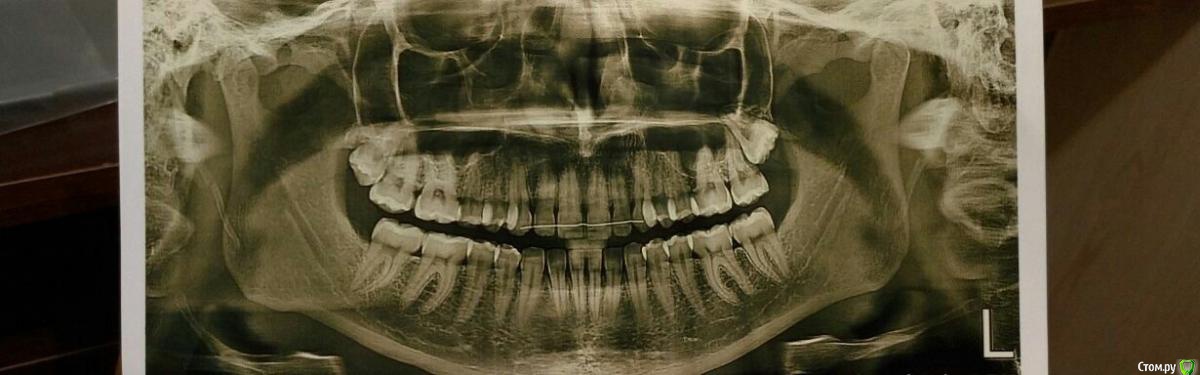

mitriy87 Опубликовано 24 июня, 2019 Поделиться Опубликовано 24 июня, 2019 Добрый день! Ситуация следующая: девушка, 25 лет, в возрасте 15 лет носила брекеты в течение четырёх месяцев. Сейчас вылез правый верхний зуб мудрости, сделали данный снимок. Стоит ли в данном случае удалять эти восьмёрки и как это может повлиять на остальные зубы? Ссылка на комментарий

red_butler Опубликовано 25 июня, 2019 Поделиться Опубликовано 25 июня, 2019 Стоит ли в данном случае удалять эти восьмёрки удалять Ссылка на комментарий